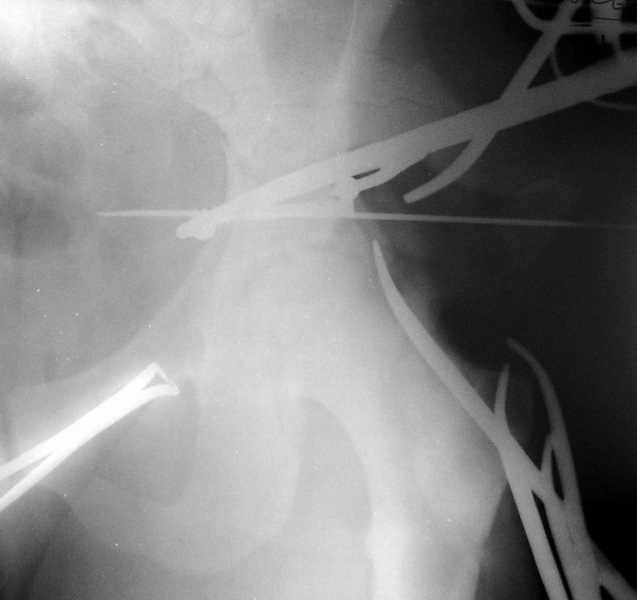

Травма 17 ноября 2002 г., поступил к нам 1 декабря, оперирован 8-го - открытая репозиция, остеосинтез пластинками и винтами. Учитывая повреждение переднего полукольца справа, и крестца и крестцово-подвздошного сочленения слева, наложили аппарат на 2 месяца.

Для экономии места привожу интра- и послеоперационный обзорный снимок, без дополнительных проекций.